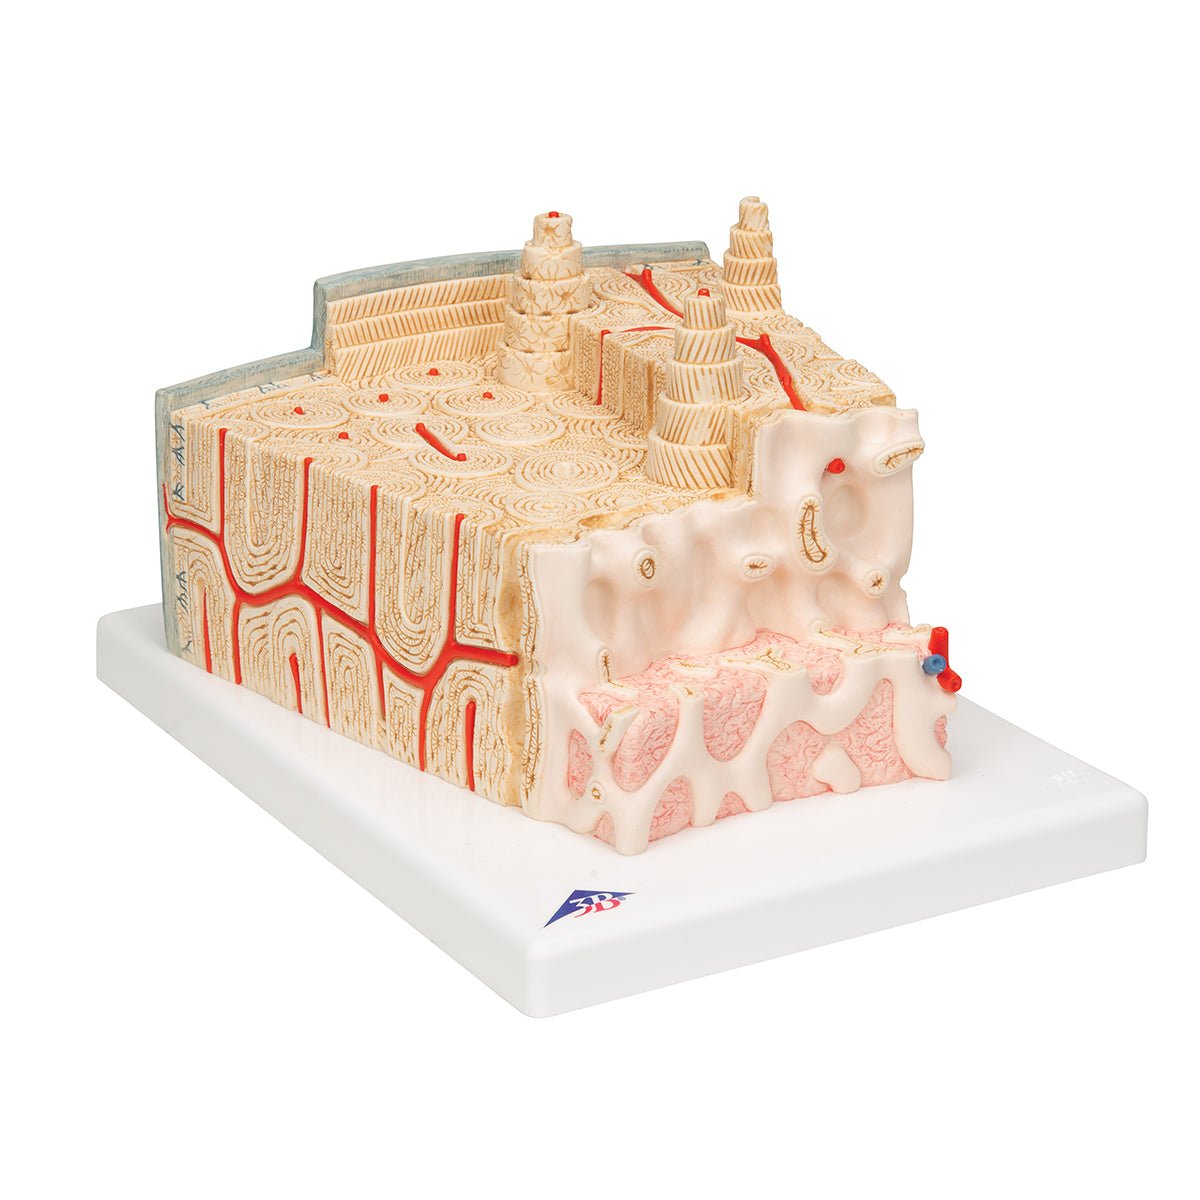

Salg af anatomiske modeller er det bærende element i eAnatomi, selvom vi også bruger mange ressourcer på at udvikle vores egne anatomiske materialer som fx plakater. Anatomiske modeller anvendes til forskellige formål og kan både vise afgrænset væv, organer samt organsystemer. Søger du en simpel model af knoglevæv eller måske en avanceret torso-model baseret på MRI teknologi, kan du finde det hele på eanatomi.com.